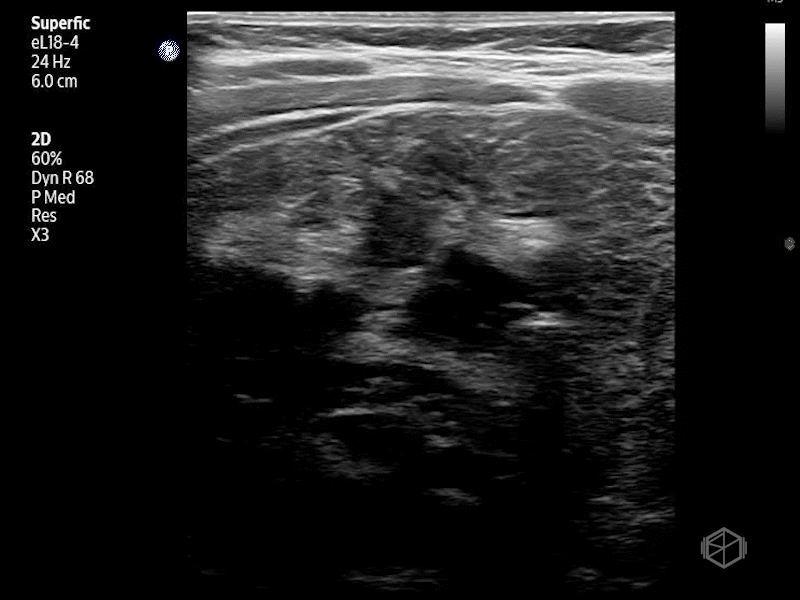

On their scan they saw:

Bedside abdominal ultrasound revealed: A “target” (donut) like structure in the right upper quadrant on transverse view. Concentric hypoechoic and hyperechoic rings representing telescoped bowel. A “pseudokidney” sign on longitudinal view. Bowel-within-bowel configuration measuring >2cm in diameter. No obvious free fluid was noted.

Diagnosis: Ileo-colic intussusception